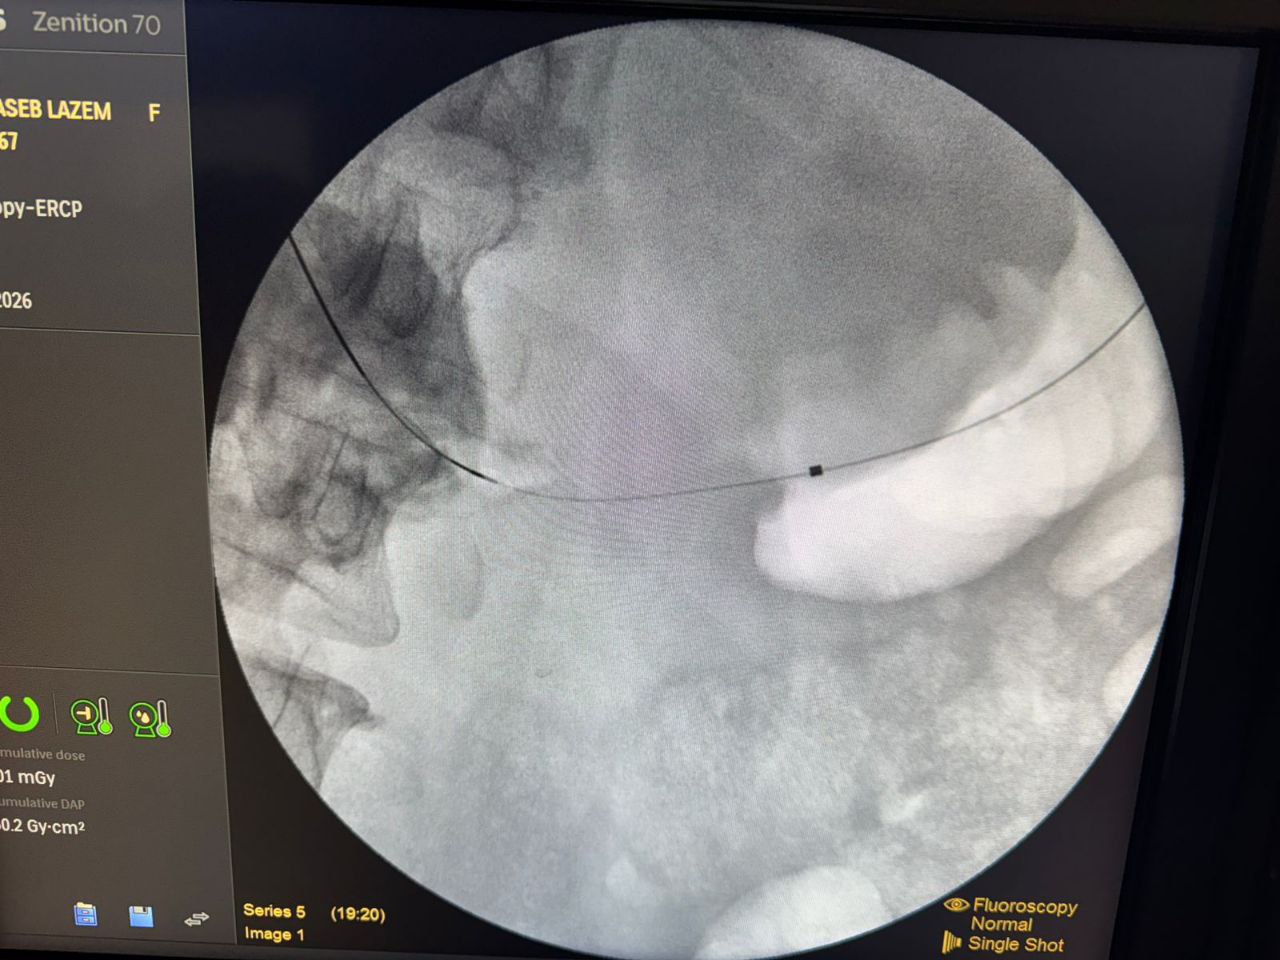

وقال رئيس هيئة الصحة والتعليم الطبي في العتبة الحسينية المقدسة الدكتور "حيدر حمزة العابدي" في تصريخ خص به وكالة نون الخبرية ان " هذه العملية هي واحدة من العمليات التي اجراها الليلة الدكتور "خالد رجب" في مركز الجهاز الهضمي بمؤسسة وارث الدولية وهي لا تجرى الا في المراكز المتقدمة في العالم، اما في العراق فلا يتم اجراءها اطلاقا"، مشيرا الى ان " العملية هي تحويل مجرى الطعام من المعدة الى الامعاء الدقيقة

من دون عملية جراحية وانما عبر ناظور الفم فقط، وتجرى للمرضى الذي يصبح لديهم انسداد في مخرج المعدة او الاثني عشري".